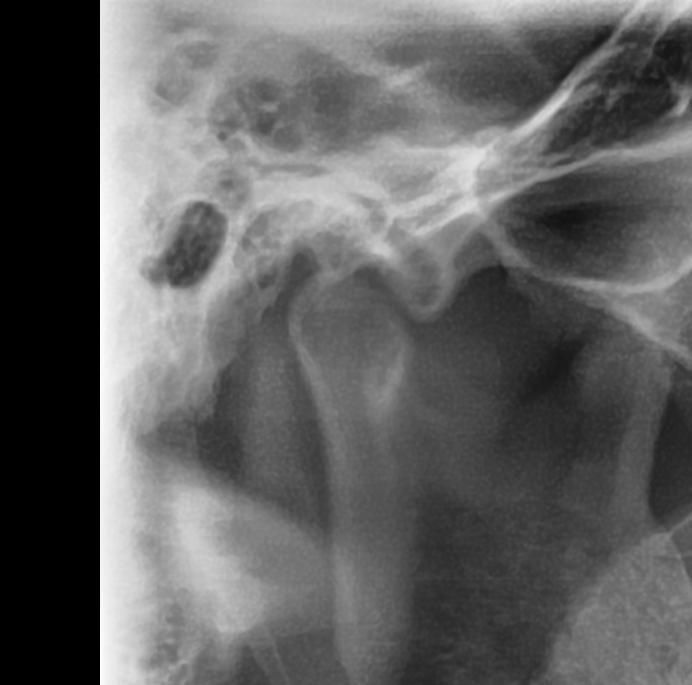

턱 관절 과두 상태 전 후 상태 한 번 봐주세요

최근에 턱 관절 통증 때문에 사진을 한 번 찍어 봤는데요 예전 사진과 비교 했을 때 어떤지 한 번 봐주시겠어요?

어떤 문제가 있는지 상세히 알려주시면 감사하겠습니다

사진1,2가 전이고 3,4가 후 입니다

• 1번 째 사진

엑스레이 상으로도 턱관절이 좋아 보이진 않습니다. 일단 구강내과를 가셔서 턱관절 정밀검사를 받아보시고 치료를 받으시는게 좋을것같습니다.

파노라마 사진으로는 턱관절을 정확하게 진단하기는 어렵습니다. 과두부분이 평평하게 되어있는 모양으로 유추해 봤을때 과두에 강한힘이 오래동안 작용했을수 있습니다. 턱관절질환은 턱관절에 가해지는 힘이 강해서 생기기 때문에 턱관절에 가해지는 힘을 줄이는것이 좋습니다.